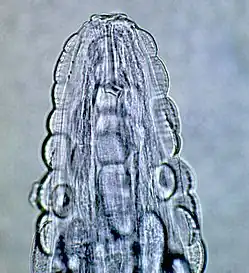

| Male Gongylonema pulchrum as seen under a light microscope.[1] | |

These are all pictures from a single Gongylonema pulchrum male extracted from a man in France.[1]

Head -